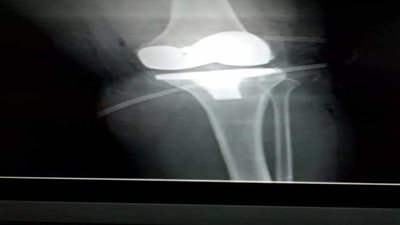

مفصل صناعي

نجاح أول عملية تركيب مفصل صناعي للركبة بتقنية الروبوت بمدينة الملك سلمان الطبية

على نفقة الدولة.. مفصل صناعي لـ"مسنة" بشبرا الخيمة